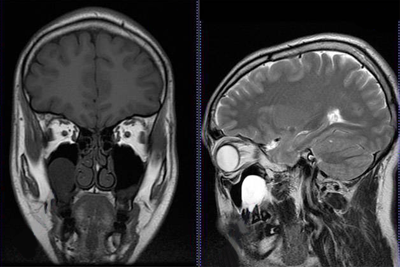

МРТ придаточных пазух носа

Магнитно-резонансная томография придаточных пазух носа – это высокоточное, безвредное исследование, направленное на выявление патологических изменений в гайморовых, лобных, основных пазухах и ячейках решетчатого лабиринта. Чаще всего МРТ проводится для уточнения диагноза, проверки эффективности назначенного врачом лечения, а также в качестве подготовки перед операцией.

Иногда, если в этом есть необходимость, проводится магнитно-резонансная томография с контрастированием. Данная процедура помогает на первом этапе отличить доброкачественную опухоль от злокачественной (хотя итоговый диагноз ставят только после биопсии), определить ее размеры и расположение.